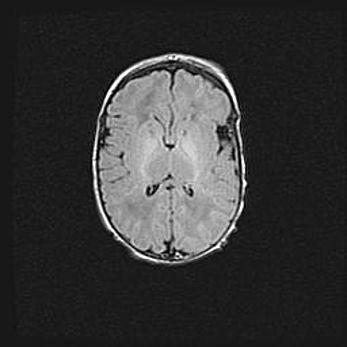

Лейкомаляция с кистозно-глиозной дегенерацией головного мозга.

Возраст: 2 месяца 25 дней

Вес: 6400 г

Окружность головы: 40 см

Срок гестации: 41 неделя

Лейкомаляцию относят к ишемически-гипоксическим повреждениям головного мозга, диагностируемым у новорожденных. При лейкомаляции в головном мозге обнаруживают очаги некроза, возникшие после тяжелой гипоксии и нарушения кровотока. В процессе морфогенеза очаги проходят три стадии: 1) развития некроза, 2) резорбции и 3) формирования глиозного рубца или кисты. Перивентрикулярная лейкомаляция (ПЛ) встречается примерно в 12% случаев среди новорожденных, обычно – у недоношенных детей, причем, частота ее зависит от массы, с которой младенец появился на свет. Наибольшее число малышей страдает лейкомаляцией, если масса при рождении 1500-2500 г.